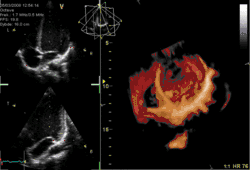

بیماریهای قلب و عروقی (CVD) معمولترین عامل مرگ در جهان در سال ۲۰۰۸ بودند که باعث ۳۰ درصد از موارد مرگ شدند.[17][18] از این میزان بیش از سه چهارم به خاطر بیماری شریانهای کرونری و سکته بودهاست.[17] عوامل خطر شامل مواردی همچون: سیگار کشیدن، اضافه وزن داشتن، عدم فعالیتهای ورزشی کافی، کلسترول بالا، فشار خون بالا، نوعی دیابت که به شکلی ضعیف کنترل شده و موارد دیگر میشود.[19] تشخیص بیماری قلبی عروقی اغلب با شنیدن به صدای قلب با گوشی پزشکی، ECG یا با اکوکاردیوگرام صورت میگیرد.[5] بیماریهای مرتبط با قلب اصولاً با متخصصین قلب درمان میشود، هرچند که بسیاری از متخصصین پزشکی دیگر نیز ممکن است در حل این مسئله کمک کنند.[18]